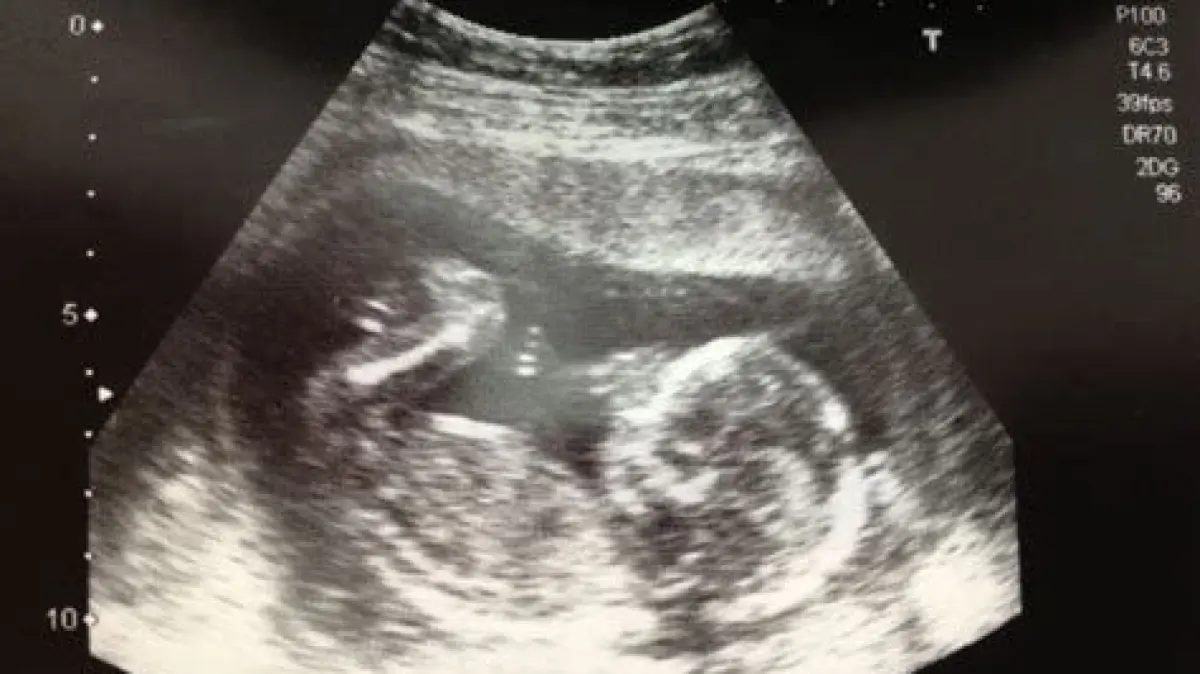

Ukuran Janin di Usia 2 Bulan

Menurut standar umum, pada usia 2 bulan (atau sekitar 8 minggu kehamilan), ukuran janin kira-kira sebesar buah raspberry atau kacang polong besar. Panjangnya sekitar 1,6 cm. Meski kecil, perkembangan yang terjadi sangatlah signifikan.

Penting diperhatikan bahwa pada usia ini, organ-organ vital seperti otak, jantung, hati, ginjal, dan tulang belakang mulai terbentuk. Jantung janin sudah mulai berdetak, dan detaknya dapat dideteksi melalui USG. Lengan, kaki, jari tangan, dan jari kaki juga mulai muncul sebagai tunas kecil.